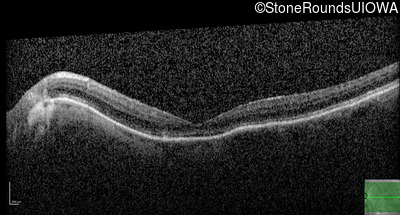

Optical Coherence Tomography - Left - 20/400

Exemplar / OCT Stack

OCT Stack